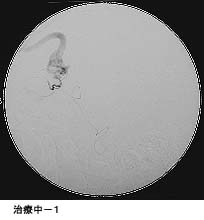

脳動静脈奇形に対する液体塞栓物質を用いた治療

治療により異常血管は閉塞されました。